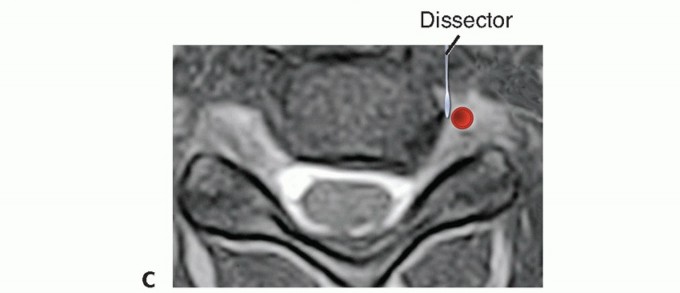

TECH FIG 5 • A,B. Vertebral artery anomalies. A. The right transverse foramen (arrow) courses somewhat more medially than the one on the left. This is a subtle but potentially important anomaly to observe preoperatively. B. The anomaly occurs within the vertebral body rather than at the disc space level where the right transverse foramen is now more normally positioned (arrow). C. Penfield lateral to the uncinate. In certain cases, especially if there is a deformity, the location of the lateral border of the uncinate (ie, the safe zone for the vertebral artery) may not be obvious after elevation of the longus colli. Placing a Penfield dissector no. 4 gently underneath the longus colli, retracting it laterally, and then hooking the dissector lateral to the uncinate will allow for safe orientation to the vertebral artery. The vertebral artery is typically in the anterior two-thirds of the disc space. When curetting disc material in this area, a vertebral artery laceration might occur if the curette strays lateral to the lateral border of the uncinate. If in doubt, a Penfield dissector can be used to identify the lateral border of the uncinate processes to avoid straying laterally and injuring the vertebral arteries, which are generally a few millimeters from the lateral edge of the uncinate (TECH FIG 5C). ### Graft Sizing and Placement Ultimate graft height can be estimated preoperatively from the preoperative lateral film. In many cases, a graft height of 2 to 3 mm more than that measured on the preoperative lateral film will be the optimal choice. Ideally, the anteroposterior depth of the graft should be a few millimeters less than that of the disc space, such that the graft can be countersunk 2 mm without entering the spinal canal. The final height of the graft can be determined after endplate preparation with sizers that accompany commercial grafts (TECH FIG 6). The trials should be lightly malleted into position under gentle Caspar pin distraction. A snug fit in the distracted position will ensure an excellent fit after removal of distraction pins. If the trial does not fit but the next smaller trial seems too loose, the surgeon should identify the area of impingement and lightly decorticate that area. Then, the trial is reinserted. For multilevel ACDF, we prefer to decompress and graft each segment before proceeding to the next level. One way to enhance fusion rates is to place as much bone into the interspace as possible. A wide decompression also provides greater room for bone graft. Space lateral to the structural bone graft in the uncinate regions can be packed with bone or bone graft substitutes. 7 If the space is wide enough, two grafts can be placed side by side to fill the entire space.